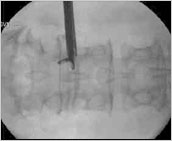

手术当中可随时X射线下确认手术部位,因而准确的确定神经根的位置避免对神经的损伤。